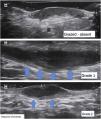

Another important complementary assessment is the grading of fibrosis (Fig. 11),16 which may appear as absent (grade 0), as a thin peripheral hypoechoic band with a fibrillar pattern (grade 1) or as a thick, peripheral hypoechoic band with a fibrillar pattern that invades the fistula lumen and produces a hypoechoic halo that is transversely visible (grade 2).

A fistula with a high degree of fibrosis is chronic and requires surgical treatment.